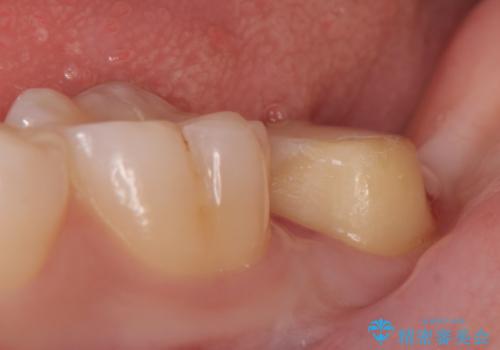

その後歯茎の治りを待ちポケットが正常値であることを確認後、オールセラミッククラウンによる補綴を行いました。

今回用いたオールセラミッククラウンはジルコニアフレームという白い素材の上にセラミックを盛っているため、審美性が非常に高いのが特徴です。

また、ジルコニアは人工ダイヤモンドの材料にも使われているほど高い強度を持っており、そのためオールセラミッククラウンは審美性だけでなく、奥歯やブリッジの補綴も可能とするクラウンです。